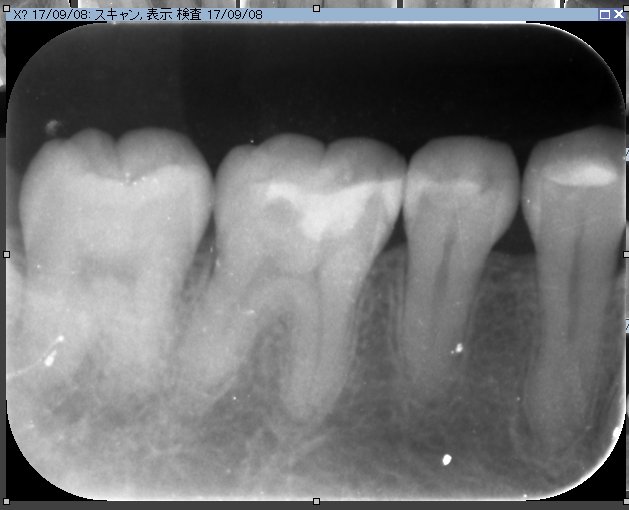

CTとデンタルをみると髄床から何か管か破折線か見えます。なんだろう。これが分岐部病変の原因ではないかと思います。歯科ドックをしたからここまでわかりました。

さて丁寧に根管を探していきます。

ん?歯髄から結石が!!これもマイクロエキスカで丁寧に取ります。

ん?近心根の中に2根(珍しい)1つは分岐部へ。

非常に珍しいケース。近心の根管の中に分岐部があり根管がご覧の様に縦に並んでいました。根管の形態はご覧の様に様々。だから時間と精密さが求められます。